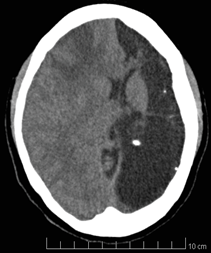

A la revisión por sistemas no se evidencian datos de interés; al examen físico paciente alerta, consciente, orientada, hidratada, sin signos de dificultad respiratoria, fuerza muscular de 3/5 en miembro superior derecho posiblemente por antecedente de polio en primer año de edad y de 5/5 en las demás extremidades, cifras tensionales de 106/63 mmHg, frecuencia cardiaca de 76 pulsaciones por minuto, frecuencia respiratoria de 18 respiraciones por minuto, ruidos cardiacos rítmicos sin soplos, ruidos respiratorios sin agregados pulmonares, abdomen blando no doloroso a la palpación, altura uterina de 31 cm, feto longitudinal cefálico derecho, con frecuencia cardiaca fetal de 155 latidos por minuto; la paciente es valorada por el servicio de ginecología quienes consideran que cursa con eclampsia pre-parto, alto riesgo obstétrico y actividad uterina pretérmino, por lo cual se continúa manejo neuroprotector con sulfato de magnesio, fenitoína y manejo antihipertensivo; además se realiza una Tomografía Axial computarizada (TC) y un electroencefalograma (EEG), este último sin alteraciones; pero de forma incidental en la tomografía axial computarizada se encuentra reemplazado casi la totalidad del hemisferio cerebral izquierdo por una gran zona de encefalomalacia quística antigua con calcificaciones puntiformes (Figura1) , asociada a desviación de las estructuras de la línea media hacia la izquierda y a importante dilatación del ventrículo ipsilateral; con preservación del tálamo y de las estructuras del tallo encefálico.

Se observa una extensa zona de hipodensidad próxima al LCR (8 uh= que se extiende por los territorios vasculares de la arteria cerebral anterior, media y posterior del lado izquierdo. Que no se asocia a efecto masa. Además de la cabeza del caudado que está delineando el contorno de asta frontal.